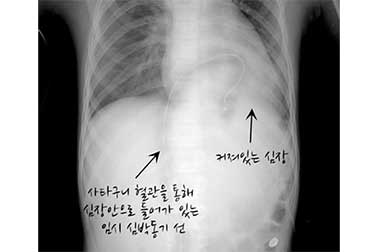

전도장애가 심한 경우, 응급 조치로 임시 심박동기 삼입이 필요할 수 있으며 회복되지 않으면 영구 심박동기 삽입이 필요할 수 있습니다.

심근염에 의한 방실 전도 장애

심근염 환자의 흉부 X-ray

감소된 심근 수축력

심근염에 의한 심낭 삼출액